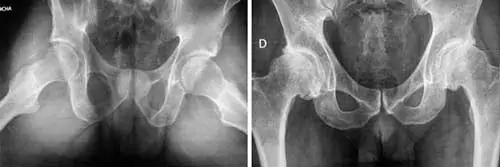

Arriba, signos de osteopatía asociados a displasia de cadera